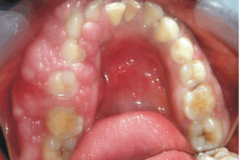

torus palatinus

-exophytic growth of normal compact bone -more common in females and native americans -genetic